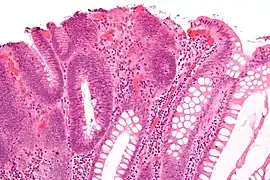

Hyperplastic polyp Colorectal (unless otherwise specified) Serrated unbranched crypts if polyps are more than 100

Serrated polyposis syndrome

Sessile serrated adenoma Colorectal Similar to hyperplastic with hyperserration, dilated/branched crypt base, prominent mucin cells at crypt base Yes